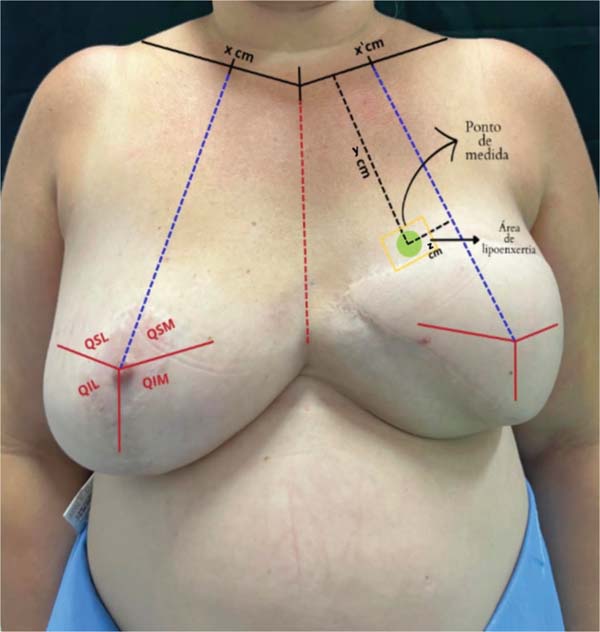

Marcação pré-operatória e definição do ponto de mensuração

Primeiro, a mama não reconstruída é dividida em quatro quadrantes, usando o mamilo como referência horizontal e uma linha vertical do ponto médio da clavícula até o sulco inframamário. Esse ponto médio também é marcado na clavícula contralateral para orientar a mama reconstruída. O centro do tórax é demarcado pela fúrcula esternal. Com um compasso de 20 cm, o ponto do mamilo original é transferido para a mama reconstruída, guiando-se pela linha esternal e permitindo a marcação dos quatro quadrantes na mama reconstruída.

Dentro do quadrante mamário com queixa de baixa volu-mização, é estabelecido um ponto fixo para mensuração da espessura subcutânea durante todo o acompanhamento. Esse ponto é definido como a região central do quadrante e a menor distância desse ponto até a clavícula e até a divisão do quadrante mamário mais próxima é registrada para que o ponto seja reprodutível nas próximas mensurações. ►Fig. 1.